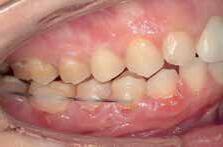

Case 1:

A 24-year-old female presented to the orthodontic clinic with the chief complaint of “Presence of space in the posterior mandibular right region”.

An intra- oral examination revealed the absence of the mandibular right first molar, tilting and oblique inclination of the mandibular second and third molar.

The patient had skeletal and dental class I, a normal overbite an overjet, slight mandibular anterior crowding, rotation of lower right first and second premolars, impaction of upper left and right third molars, and mandibular left third molar.

The patient recalls an extraction that was carried out during childhood but couldn’t specify exactly if it was the mandibular right first molar.

A panoramic x-ray showed the absence of the right first mandibular molar, a 45 degrees inclination of the second and third mandibular right molars, a vertical bone defect at the old extraction site, with a large composite filling on a endodontically treated mandibular left first molar.

Non extraction treatment, with mesial root movement and protraction of the mandibular second and third molars in order to close the residual space, create a solid contact between the mandibular second molar and second premolar without the need for prosthetic dental implant or crown. This option would require longer orthodontic treatment time with extensive follow up visits, however no extra cost is allocated for surgical and prosthetic procedures. (Figures 1 and 2)

Figure 1 Figure 2